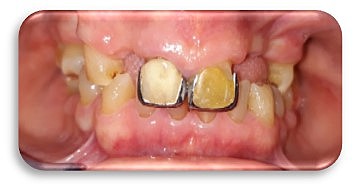

Paciente femenino de 64 años de edad, acude con motivo de consulta: "Quiero tener una bonita sonrisa". se recolectan los datos del paciente. con problemas de obesidad.

• Modelos de estudio y  fotografías intraorales

Modelos de estudio y fotografías intraorales

Referencia a una réplica exacta de la estructura dental del paciente.